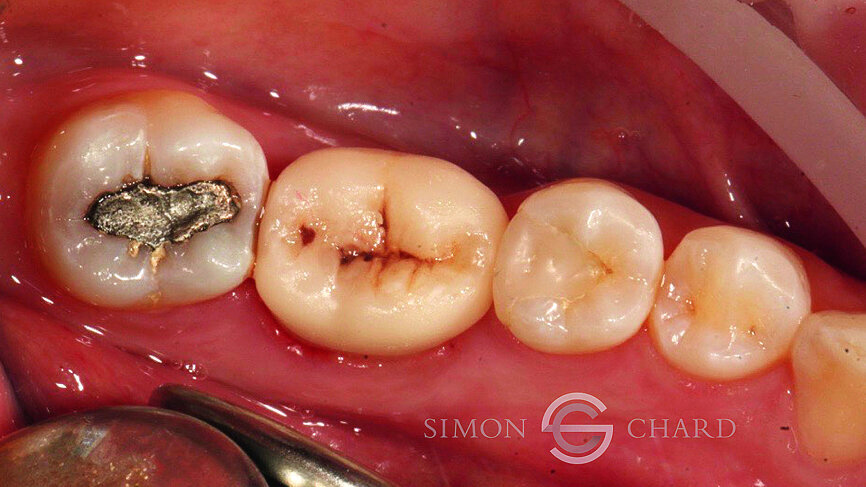

This case report highlights a novel method of restoring implants utilising the modern advances in digital intraoral scanning and chairside milling. It illustrates how an aesthetic single implant retained crown can be provided chairside without the need for analogue impressions (Figs. 1 & 2: Pre-operative condition).

Following a discussion of the options for replacement of LR6, the patient elected for an implant-retained solution. A MegaGen AnyRidge 4 x 10 mm implant was placed utilising a surgical guide for position of the pilot hole. An immediate temporary crown was fabricated using the MegaGen fuse abutment and DMG Luxatemp. A silicone index of the diagnostic wax-up was fabricated and the temporary crown was polished and taken out of occlusion while the implant fully integrated (Fig. 3).